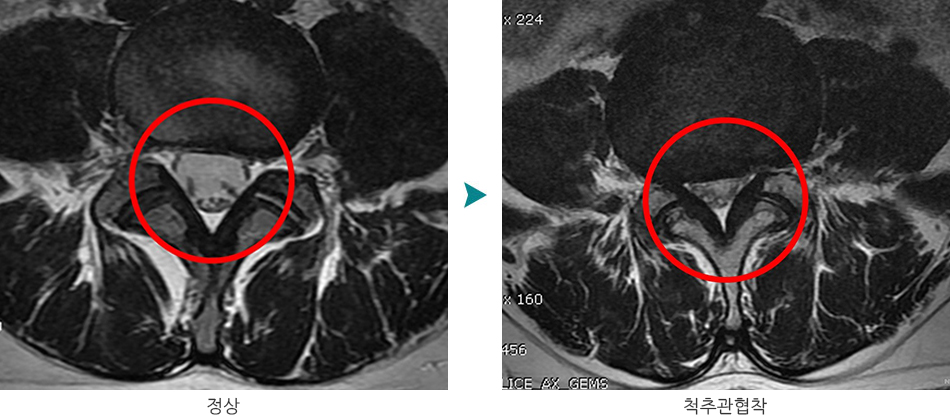

- 📌 신경 압박 정도 확인: MRI/CT 검사로 디스크 탈출 정도 재평가